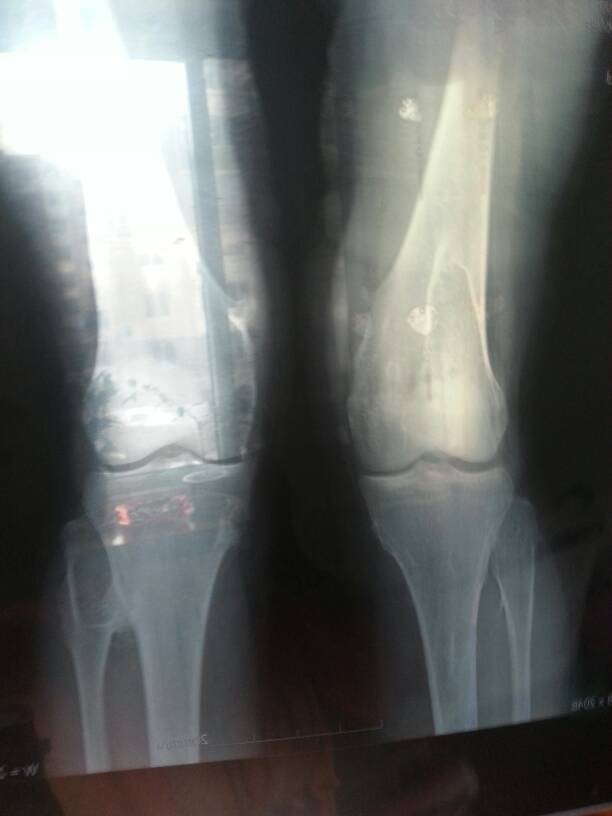

病情分析: 您好!多发性软骨瘤是良性的。 指导意见: 有可能遗传,不过多发性软骨瘤是良性病变,也没办法预防。多发性软骨瘤病为一种常染色体显性遗传性疾病,大多数病员有家族遗传史,男性多见。在男性,患病和遗传能力同时表现;在女性,疾病可潜伏或不明显,但却可传递给后代。祝您健康快乐!